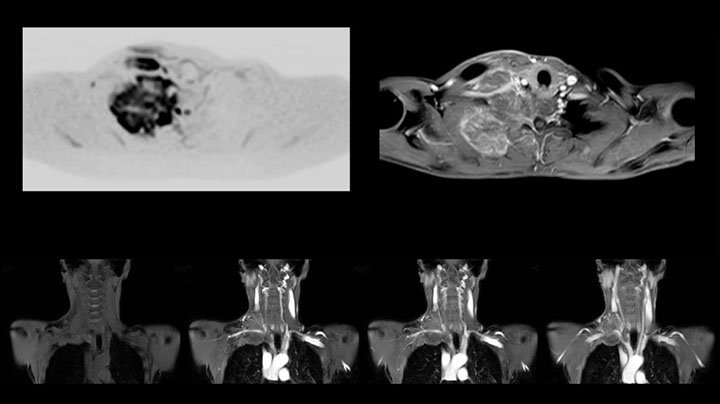

Whole body diffusion

A 61-year-old female with a malignant lymphoma underwent an MRI exam with whole body diffusion weighted imaging (DWIBS) as well as PET. On the images shown, the resolution of DWIBS is better than PET, which allows visualization of the small pelvic lesions and almost no distortion is seen in the neck area.

Prodiva MRI whole body DWI lymphoma, Seirei Mikatahara

Prodiva MRI whole body FDG-PET, Seirei Mikatahara